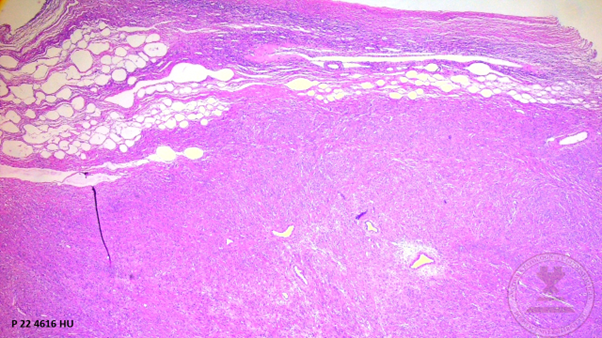

Histological images

1. Macroscopic description: adnexal tumor and right salpingus weighing 395g, with a smooth whitish surface alternating with rough areas and congestive vessels on its surface.

1. Macroscopic description: On section, the cut surface is solid, light brown in color with a swirled appearance with confluent whitish septa.

1. Panoramic view of the ovary showing the ovarian capsule, proliferation of bundles of spindle cells surrounded by a collagenous stroma accompanied by medium-caliber vessels. (HYE, 4x).